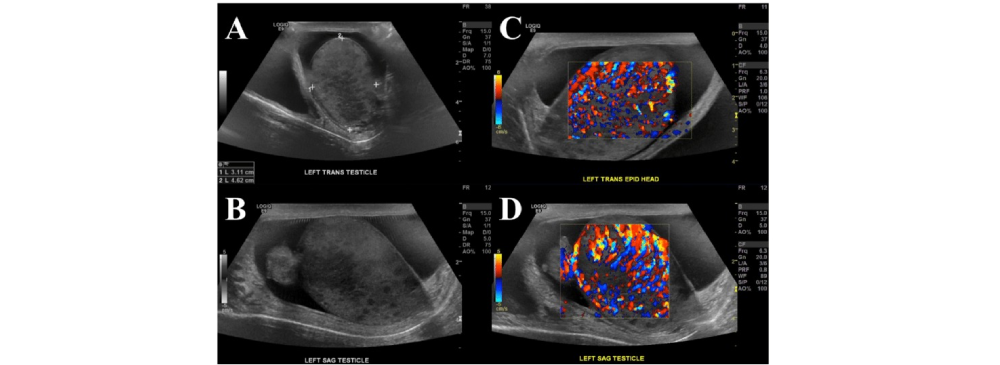

A scrotal ultrasound, also known as a testicular ultrasound, is a specialized diagnostic imaging procedure that produces detailed pictures of the scrotum and its internal structures. The procedure involves applying a water-based gel to the scrotal area, allowing sound waves to travel efficiently as a handheld device called a transducer glides across the skin. These sound waves bounce back to create real-time images, which our radiologists interpret with precision.

This test plays a crucial role in men’s reproductive health by identifying lumps, swelling, injuries, or abnormalities that may not be detected through a physical exam alone. Because it is non-invasive, painless, and safe, scrotal ultrasound is one of the most trusted first-line investigations recommended by doctors for men of all ages experiencing scrotal concerns.

A scrotal ultrasound can help diagnose a wide range of conditions, making it an essential test in men’s healthcare. For example, hydrocele refers to the buildup of fluid around the testicles, while varicocele is the enlargement of veins in the scrotum that can affect fertility. More urgent conditions like testicular torsion — where the spermatic cord twists and cuts off blood supply — require immediate diagnosis and intervention to prevent permanent damage.

At Insight Diagnostics Pallavaram, we regularly use scrotal ultrasound to evaluate cases of pain, swelling, infection, and unexplained lumps. Detecting these conditions early provides a significant advantage in treatment and helps avoid complications later. By offering accurate imaging, we help both doctors and patients make informed decisions about next steps in care.